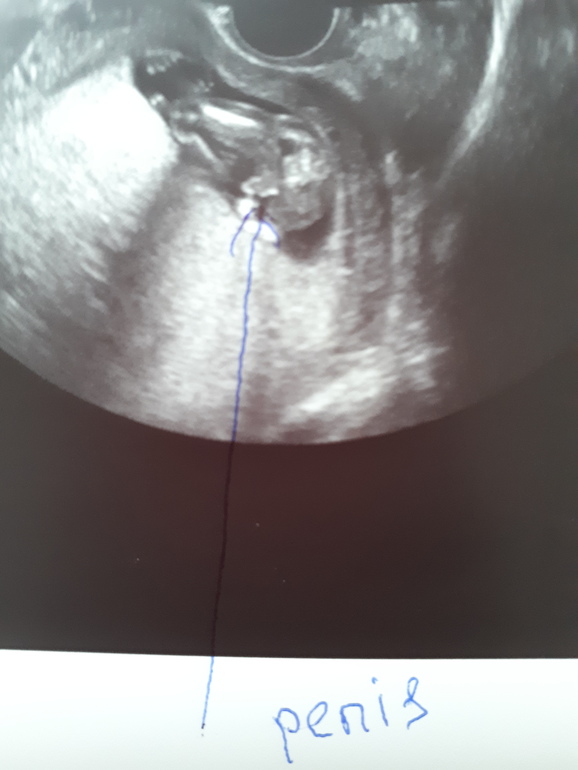

Сын! Наш Никитосик!